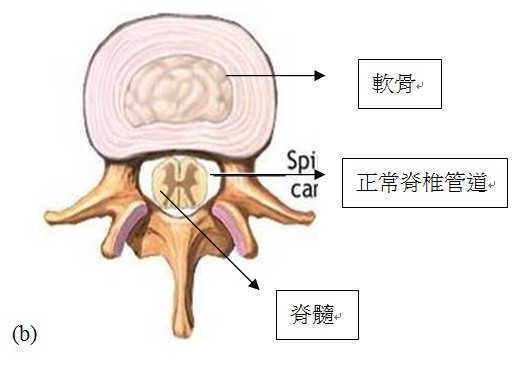

脊椎的構造

我們的脊椎是由多個能活動的脊椎骨所組成,令身體可站立丶彎腰及轉動,同時脊椎骨也能保護我們的脊髓。在每一個脊骨的中間,都有一個脊椎管道(Spinal Canal),脊髓就是在這個脊椎管道內幫助我們傳遞信息,當腦部發出的信息經脊髓到脊骨神經,通往身體各部分。

脊椎管道狹窄 正常脊椎管道